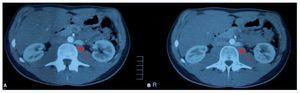

Varón de 17 años, derivado a nefrología para estudio de microhematuria. Desarrollo durante la infancia normal salvo por enuresis a los 16 años. No tenía antecedentes de infecciones urinarias previas ni de infecciones faringoamigdalares de repetición. En la analítica inicial presentó: creatinina 0,9 mg/dl, aclaramiento de creatinina 122,9 ml/min/1,73 m2; albuminuria 40,1 mg/gCr y 68,8 mg/día, proteinuria 109,2 mg/gCr y 187,2 mg/día, sedimento normal, urocultivo negativo, estudio inmunológico negativo. Tres meses después mostró un discreto incremento en albuminuria (64,4 mg/gCr y 135,3 mg/día) y proteinuria (145 mg/gCr y 304,7 mg/día). En la radiografía de tórax destacaba un leve pectus excavatum, sin observar patología cardíaca con ecocardiografía. En ecografía abdominal se observaron riñones de aspecto y tamaño normales, con pelvis extrarrenal turgente. En la angio-TC se visualizaron riñones de tamaño normal destacando una vena renal izquierda con drenaje en vena cava inferior tras seguir un trayecto retroaórtico. Su calibre estaba aumentado desde el riñón hasta su llegada a la aorta, momento en que sufría un afilamiento al pasar entre aorta y columna vertebral (fig. 1A y B). Esta anomalía ha sido denominada síndrome de cascanueces posterior. Un año después, la analítica no mostraba proteinuria ni albuminuria.

Figura 1. Imágenes de angio-TC. A) Se visualiza vena renal izquierda que se afila en su paso entre aorta y columna en su camino hacia la cava inferior. B) Se observa el tránsito de una vena renal izquierda de calibre aumentado, con trayecto descendente, que pasa por detrás de la aorta.